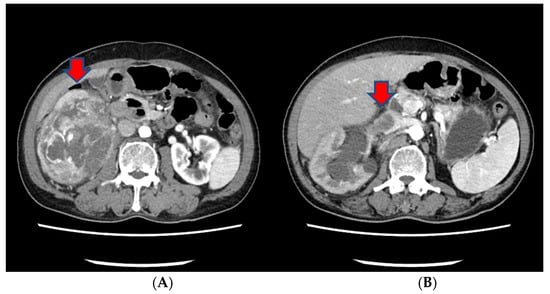

However, in a subsequent CT scan performed approximately 4 months later, an increased size of the mass in the penis was observed, and persistent penile pain led to the consideration of radiation therapy (Figure 4). After radiation therapy, a follow-up CT scan showed a decreased tumor size (5.1 cm to 3.4 cm) (Figure 4).

Figure 4.

(A) A subsequent CT scan performed approximately 4 months later showing an increased size of the mass in the penis. (B) After radiation therapy, a follow-up CT scan showed the decreased size of the tumor.